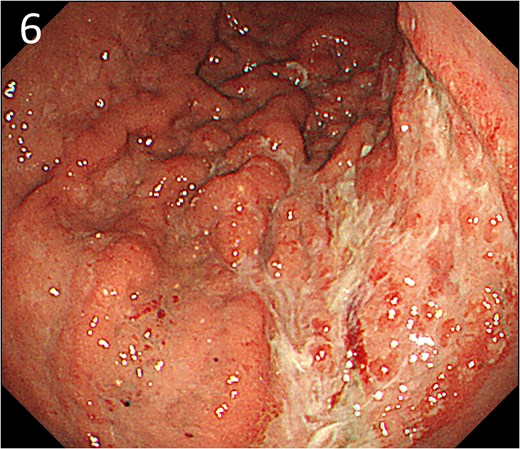

A 78-year-old man was transferred to our hospital because of hypovolemic shock. He had already received 10 units of RBC concentrate. His blood pressure was 97/64 mmHg. The patient’s haemoglobin level was 8.2 g/dL. Contrast-enhanced CT showed active contrast extravasation in the stomach (Fig. 4). Emergency angiography revealed tumour staining in both the left and right gastroepiploic arteries, which were coil embolized (Fig. 5). Upper GI endoscopy 2 days later revealed a type 4 tumour without bleeding (Fig. 6). The patient was diagnosed with resectable GC, and underwent laparoscopic total gastrectomy with Roux-en-Y reconstruction and lymph node dissection. The final histopathological diagnosis was T4aN3aM0 stage IIIC. Macroscopic findings revealed a type 4 tumour of the stomach, and histopathological findings revealed that the tumour was a poorly differentiated adenocarcinoma with squamous cell differentiation. All surgical margins were negative. The patient developed a minor leakage that resolved spontaneously. The patient has remained recurrence-free for 12 months.

Endoscopy after embolization showing a type 4 tumour without bleeding.